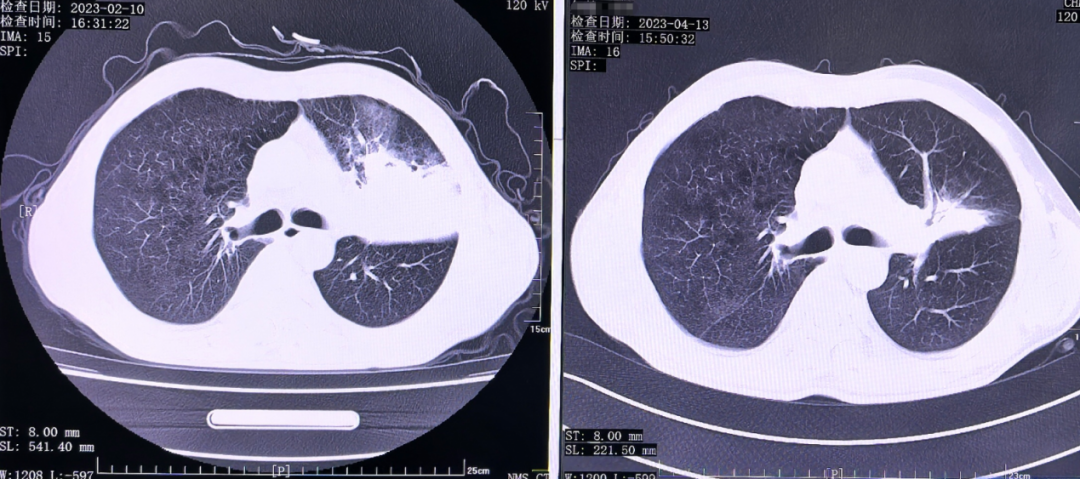

2023 年初,王先生因持续咳嗽、发热来到医院就诊。CT 影像显示:左肺上叶一片模糊,肿瘤阻塞了支气管,导致远端肺叶塌陷——医学上称为「肺不张」。

治疗两个周期后,王先生的复查 CT 显示:左肺上叶不张明显缓解,肿瘤显著缩小。

「肺不张的缓解是一个重要指标,」戴云说,「这说明肿瘤缩小后,原本被堵塞的气道重新通畅,空气能够进入远端肺组织,使塌陷的肺重新张开。」